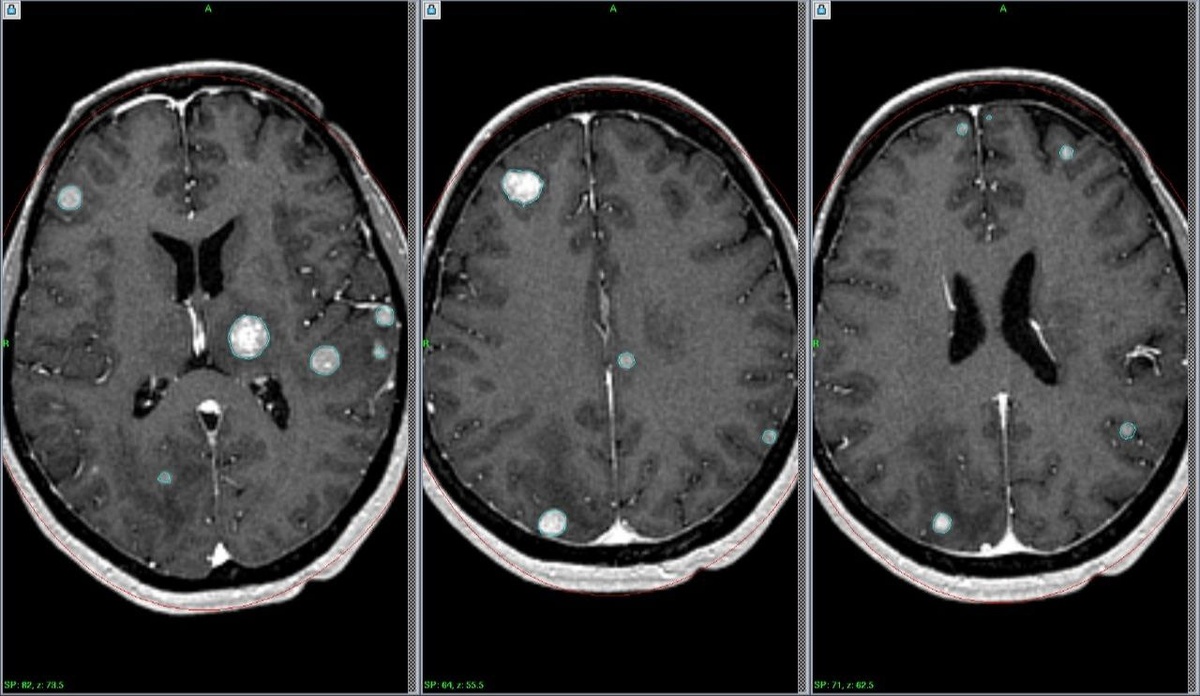

МРТ картина множественных метастазов в головной мозг.